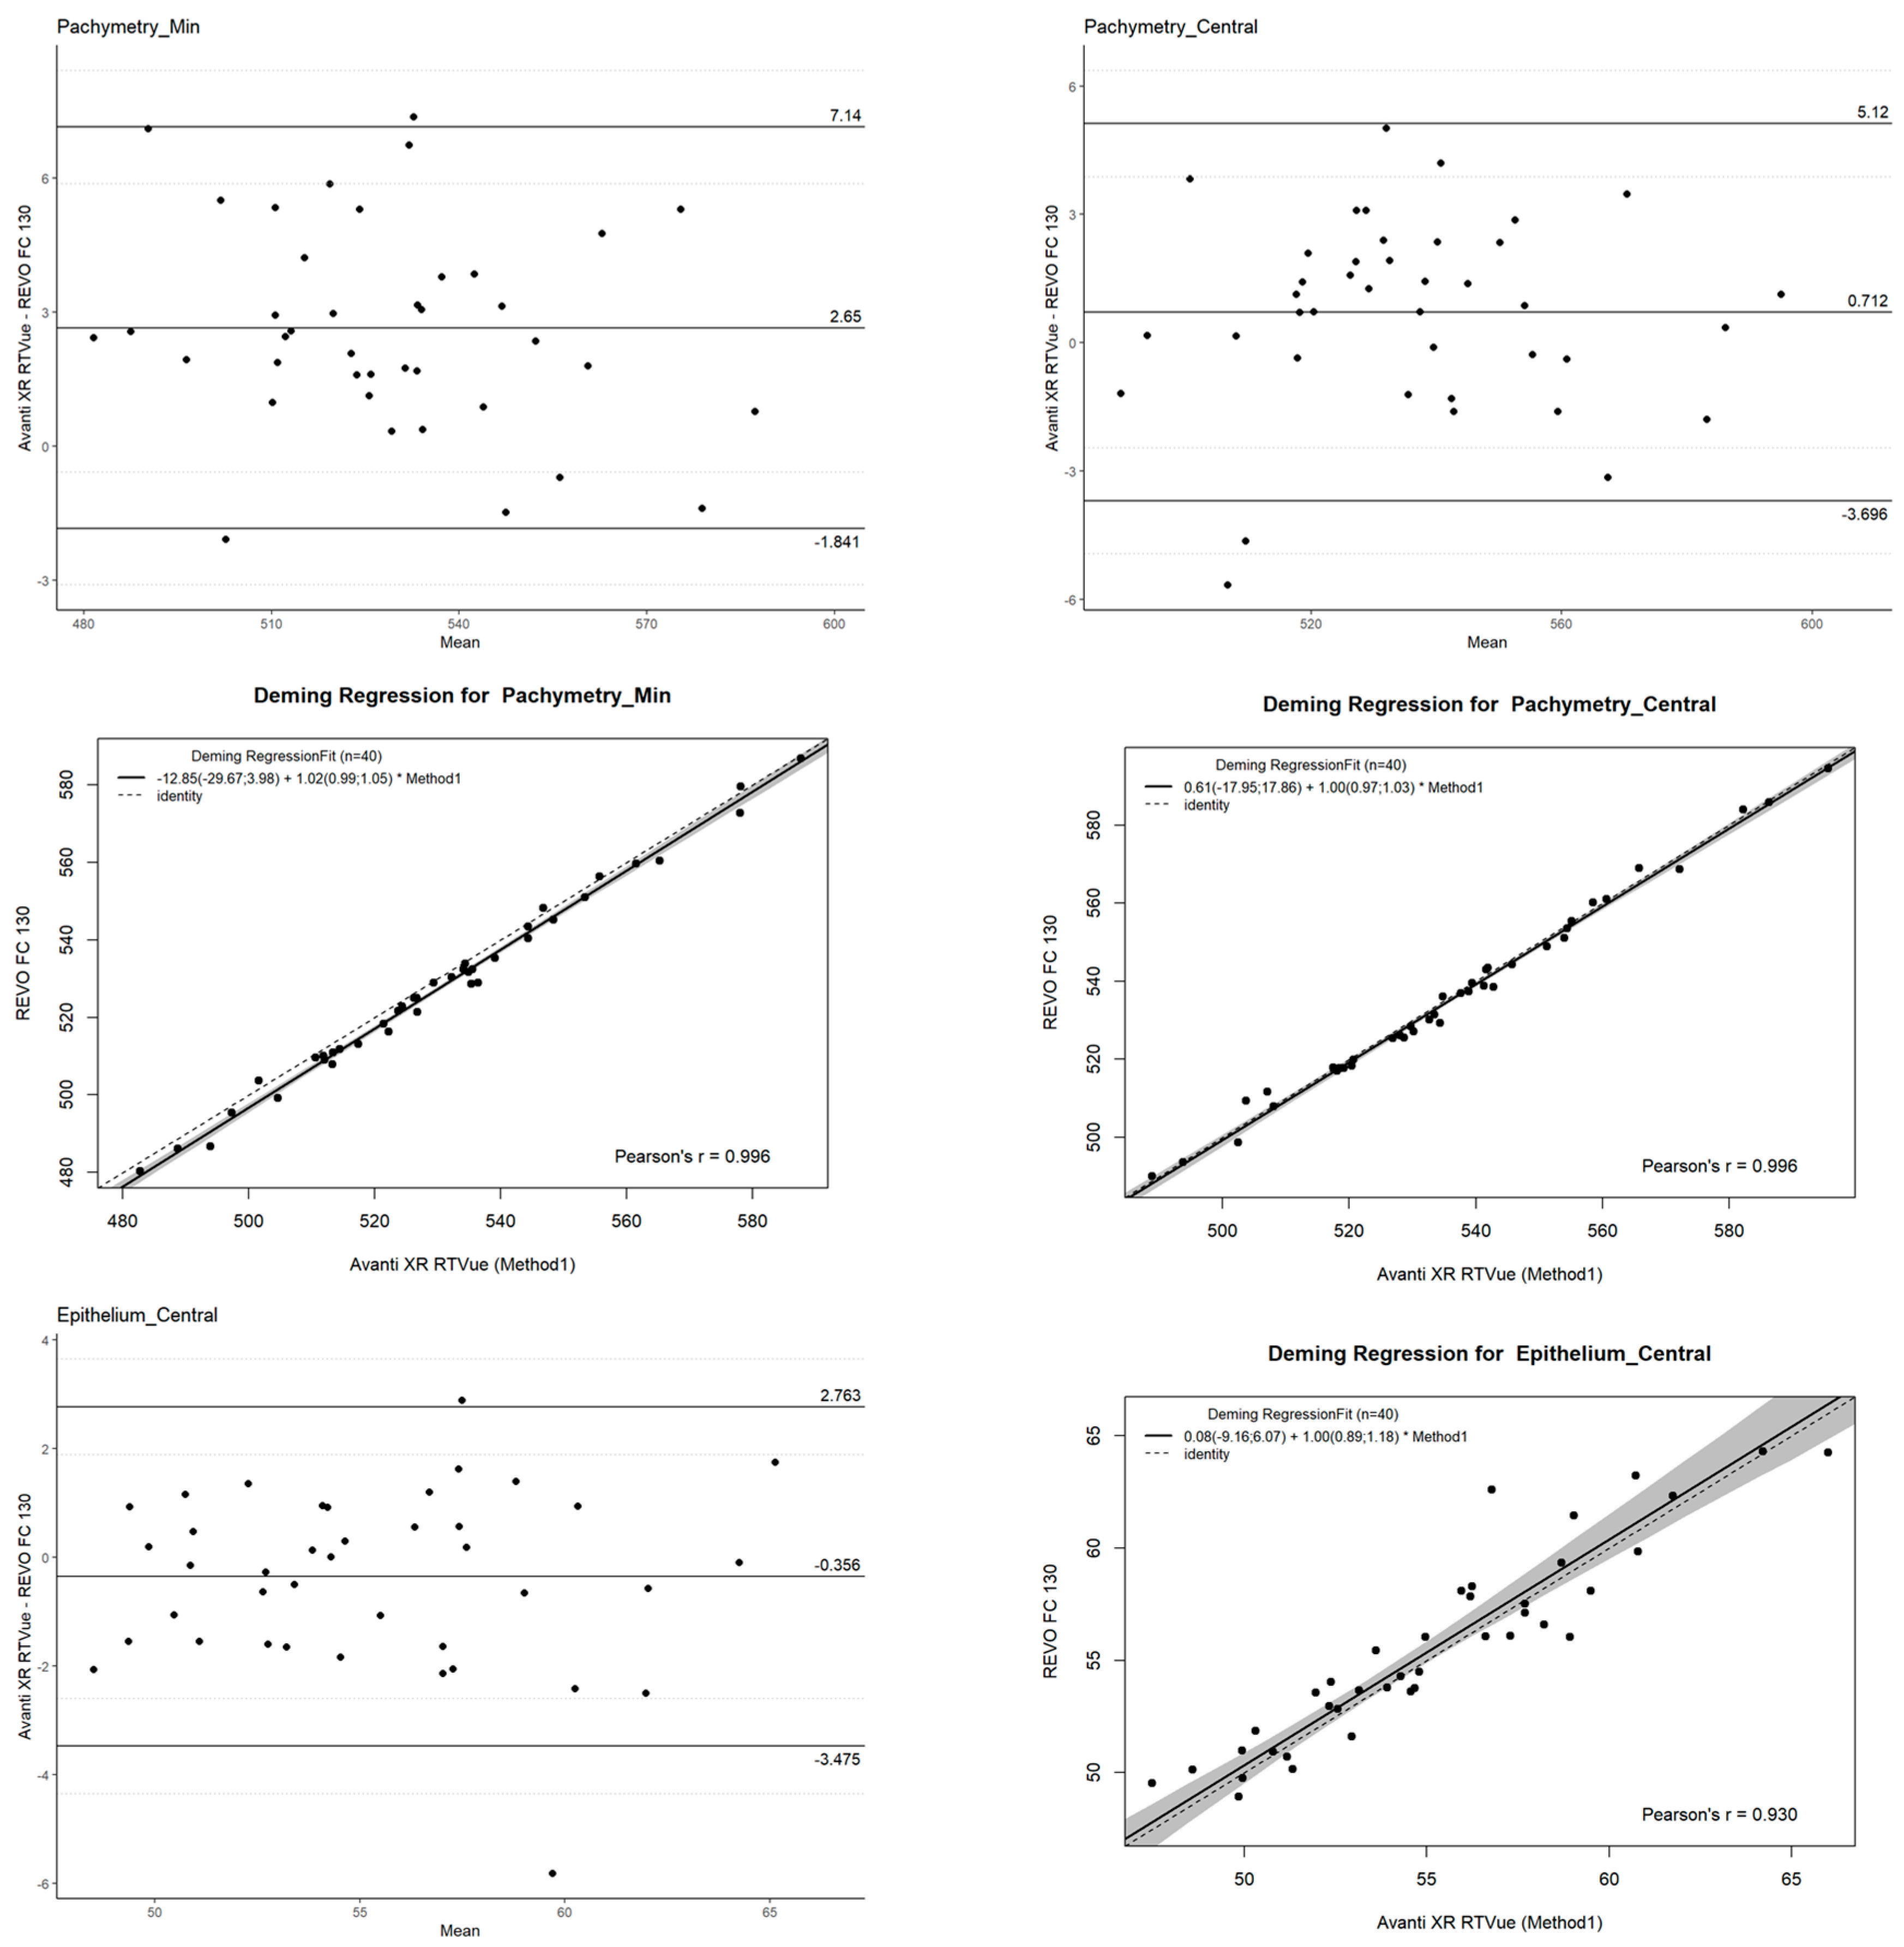

2.4. Agreement

- Mean difference (bias): Representing the systematic difference between the two devices.

- Limits of Agreement (LOAs): Defined as the mean difference ±1.96 standard deviations (SD), providing the range within which 95% of differences between measurements are expected to lie.

- Confidence Intervals (CI): Calculated for the LOAs to provide an estimate of their precision and reliability.

3. Results